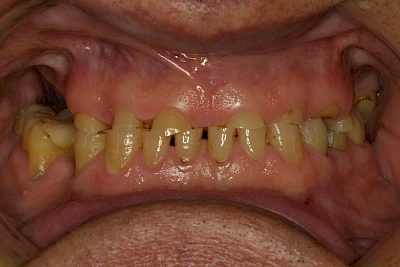

Über die Zeit können verschiedene Prozesse die Zahnhartsubstanzen aufzehren:

- Abnutzung durch Kauen (Abrasion) oder duch durch übermäßiges Knirschen bzw. Pressen (Attrition)

- Säurebedingte Auswaschung (Erosion)

- Knirschen bzw. Pressen und ungünstige Putztechnik (Druck): keilförmige Defekte

Auswaschung (Erosion) dagegen ist eine Verschleißerscheinung der Zähne aufgrund von immer wiederkehrenden Säureangriffen durch die Nahrung, verstärkt zum Beispiel durch den Genuss säurehaltiger Getränke oder Speisen. Auch bei Menschen mit einer Essstörung (z. B. Bulimie) können die Zähne durch die Magensäure ausgewaschen erscheinen.